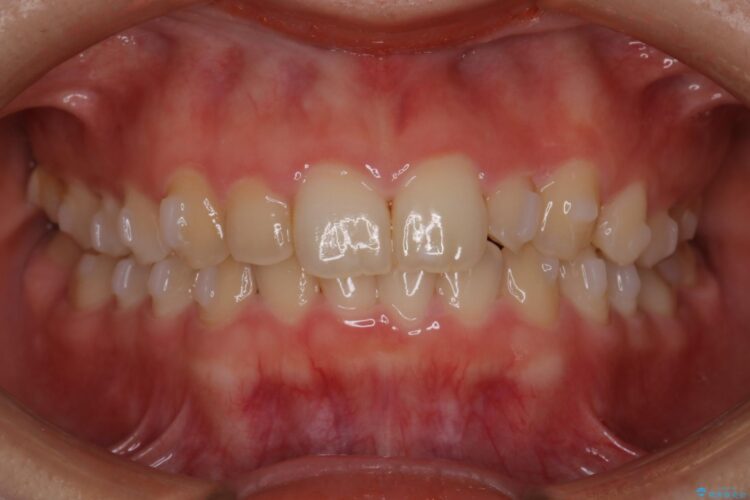

下の前歯のガタつきと正中のズレが気になるとご来院された患者様です。

その際、正中を合わせることは難しいことを説明させていただき、患者様にご理解いただいた上で治療を開始しました。

前歯のガタつきを改善するのに時間がかかりましたが、ガタつきもかみ合わせも綺麗になりました。

患者様の希望で、矯正終了後にホワイトニングも行い歯の色味も自然な白さになりました。